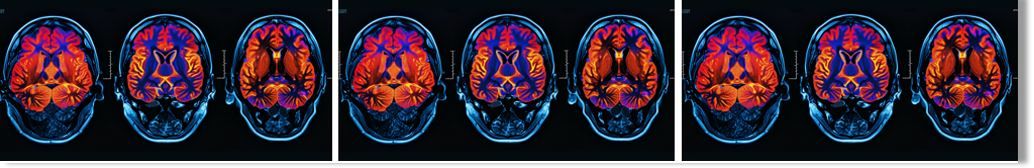

Currently, there are 3 amyloid PET tracers approved by the FDA for detecting amyloid plaques in the brain. For tau PET imaging, the newer technique, the first tau tracer used to identify tau tangles, was approved in 2020. These tools allow for earlier and more precise diagnoses, which are critical for identifying candidates for disease-modifying therapies that target early stages of Alzheimer’s.1